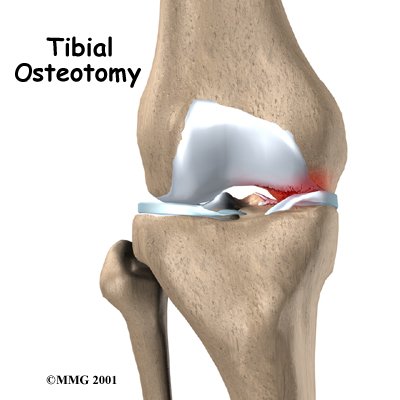

Knee osteoarthritis often affects only one side of the knee joint. When this occurs, realigning the angle made between the bones of the leg can shift your body weight so that the healthy side of the knee joint takes more of the stress. The procedure to realign the angles of the lower leg is called a proximal tibial osteotomy.

Osteoarthritis of the knee sometimes affects one side of the knee far more than the other. While either side can suffer greater damage, usually the inside half of the knee joint (the medial compartment) is more affected. When this uneven damage occurs to one side of the knee, the other side may still have good cartilage on the joint surfaces.

In some cases, surgery to realign the angles in the lower leg can result in shifting pressure to the other, healthier side of the knee. The goal is to reduce the pain and delay further degeneration in the weaker half of the knee.

There are two methods to realign the knee joint. One involves taking out a wedge of bone; the other involves adding a wedge of bone. Any operation for cutting through a bone is called an osteotomy. In a closing wedge osteotomy, the surgeon cuts though the tibia on the lateral side, removes a wedge of bone, and pins the open edges together. In an opening wedge osteotomy, the surgeon cuts though the tibia on the medial side and opens a wedge, adding a bit of bone graft to hold the wedge open.

There are two methods to realign the knee joint. One involves taking out a wedge of bone; the other involves adding a wedge of bone. Any operation for cutting through a bone is called an osteotomy. In a closing wedge osteotomy, the surgeon cuts though the tibia on the lateral side, removes a wedge of bone, and pins the open edges together. In an opening wedge osteotomy, the surgeon cuts though the tibia on the medial side and opens a wedge, adding a bit of bone graft to hold the wedge open.

There are two methods to realign the knee joint. One involves taking out a wedge of bone; the other involves adding a wedge of bone. Any operation for cutting through a bone is called an osteotomy. In a closing wedge osteotomy, the surgeon cuts though the tibia on the lateral side, removes a wedge of bone, and pins the open edges together. In an opening wedge osteotomy, the surgeon cuts though the tibia on the medial side and opens a wedge, adding a bit of bone graft to hold the wedge open.

There are two methods to realign the knee joint. One involves taking out a wedge of bone; the other involves adding a wedge of bone. Any operation for cutting through a bone is called an osteotomy. In a closing wedge osteotomy, the surgeon cuts though the tibia on the lateral side, removes a wedge of bone, and pins the open edges together. In an opening wedge osteotomy, the surgeon cuts though the tibia on the medial side and opens a wedge, adding a bit of bone graft to hold the wedge open.